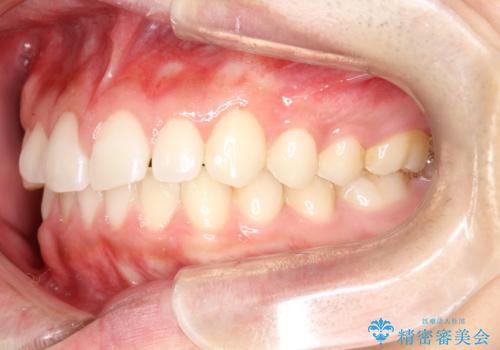

前歯の隙間がきになる インビザラインですきっ歯の治療

- 上の前歯の隙間を主訴に来院されました。

正中に隙間があり、かみ合わせが深い過蓋咬合という状態でした。

インビザラインにて矯正治療を行いました。

しっかり使っていただけたので、スムーズに治療を終了することができました。